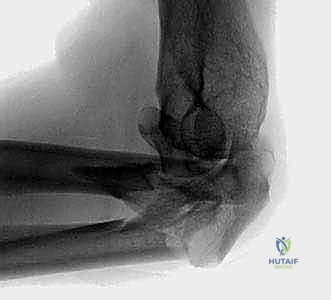

FIG 1 • Plain AP radiograph typically demonstrates fracture pattern.

FIG 1 • Plain lateral radiograph typically demonstrates fracture pattern.

FIG 1 • Plain oblique radiograph typically demonstrates fracture pattern.